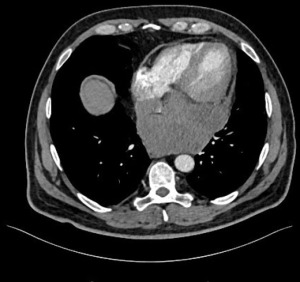

Patient 2 was a 33-year-old male who presented with coughing and a sudden decline in exercise capacity. Transthoracic and transoesophageal echocardiography revealed a large lesion of the middle mediastinum. On axial CT imaging, it measured 84 mm and was located anteriorly to the tracheal carina, compressed cephalad the right pulmonary artery and caudally the left atrium and oesophagus (Figure 2).

EBUS-TBNA was inconclusive and mediastinoscopy was performed in another hospital. Histopathological examination revealed a synovial sarcoma. Staging was completed with CT of the abdomen and did not reveal distant metastases. He underwent 6 cycles of chemotherapy with doxorubicin and ifosfamide. Re-staging chest/abdomen CT showed partial remission. On magnetic resonance imaging (MRI) of the chest/heart, the tumor shrunk down to 2.5 cm × 4 cm × 4 cm and there was no clear evidence of heart invasion.

Posterolateral thoracotomy was performed in the fourth intercostal space. After having freed the tumor from the lung with a lung wedge resection, tumor was sharply freed from the trachea-right main bronchus and superior vena cava. The azygos vein was sacrificed. Dissection was pursued intrapericardially. Evidence of infiltration of bilateral upper and lower veins, left atrium and right atrium at the junction with the inferior vena cava made a complete tumor resection impossible. Debulking was performed. Histopathological assessment confirmed a G2 monophasic synovial sarcoma. Patient was discharged on postoperative day 3. He underwent chemoradiation with 7 cycles of cisplatin and 70.2 Gy. One month later, mediastinal as well as pleuropulmonary progression were identified. Palliative radiotherapy was administered to the pleura (40 Gy) and the mediastinum (40 Gy) followed by maintenance chemotherapy with trofosfamide. Treatment was switched to pazopanib at new progression. The patient died 13 and 8 months after initial diagnosis and surgery, respectively.